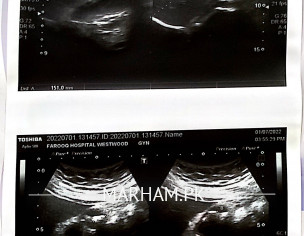

I have multiple calculi in Gall bladder, largest one is 11mm. I am wondering if any medication is effective or laser breakdown of stones is possible instead of removal of gall bladder. I have started taking spasfon, caflam 50, pelton V and teph 20.

Attach Photo here: